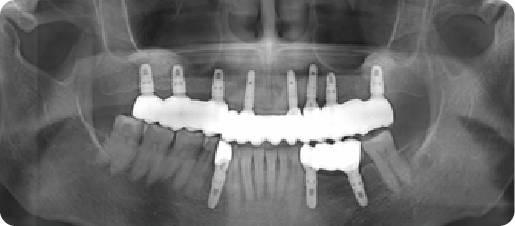

A case of generalized mobility in the remaining teeth and complete edentulism.

BEFORE

VS

AFTER

Name:Mr PanAge:62

Evaluation: Wearing a removable denture over the long term can loosen and eventually cause the loss of your natural teeth, which can significantly diminish your appetite.

Treatment Plan: The treatment involved extraction of the residual mobile teeth and immediate placement of 12 implants with a fixed prosthesis.

Patient Feedback: It feels solid—I can bite with confidence. My healthy teeth were left alone, and they look so natural and feel so comfortable, it's just like having my own teeth back

For Prevention:Keep up with your check-ups and practice good oral hygiene to prevent gum problems and extend the life of your teeth